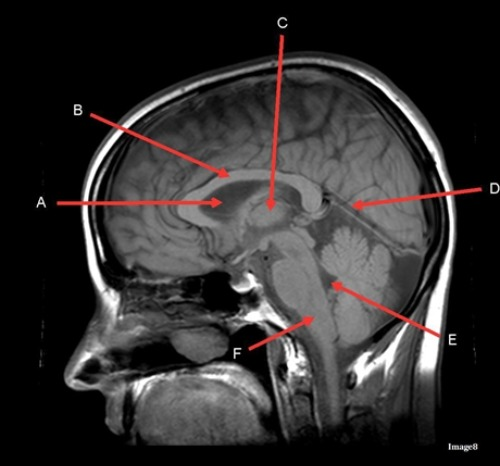

Letter C in image 8 is pointing to:

A. Tentorium

B. Corpus callosum

C. Thalamus

D. Fourth Ventricle

E. Medulla oblongata

Letter D in Image 8 is pointing to:

B. Cerebellum

Letter A in Image 8 is pointing to:

C. Hypothalamus

E. Lateral Ventricle

Image 8 is an example of a ____ weighted sequence acquired in the ____ scan plane.

A. T1; Axial

B. T1; Sagittal

C. T2; Axial

D. T2; Sagittal

Letter B in Image 8 is pointing to:

Letter E in Image 8 is pointing to:

Letter F in Image 8 is pointing to: